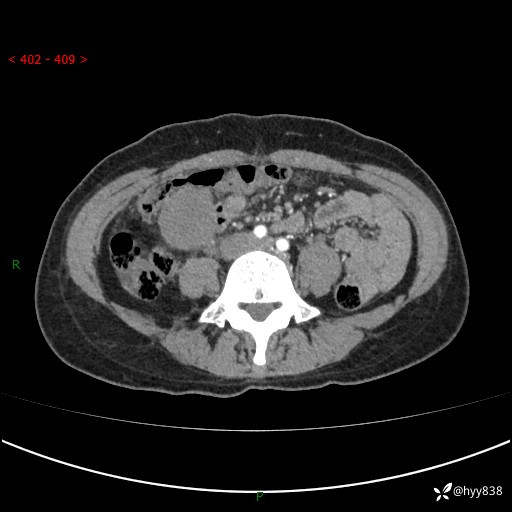

年轻女性,发现腹腔肿物1周。圆圆的肿物,诊断有难度---结果公布~

现病史:患者自诉于1周前无明显诱因出现剑突下间断性隐痛,尚可忍受,不向其它部位放射,无恶心呕吐、腹泻便秘等不适,于当地市第二人民医院就诊,行CT结果示:1.右中腹占位,间叶组织来源可能2.小肠梗阻3.盆腔积液4.腹腔积液5.副脾6.肝囊肿;于荆州二医行抗炎,抑酸,护胃,补液等对症支持治疗;患者病情好转,今为求进一步诊治,遂来我院门诊就诊,门诊以“腹腔肿瘤”收入院。 起病以来,患者精神、睡眠、饮食一般,大小便正常,近期体力体重无明显改变。

腹部CT增强(外院平扫)